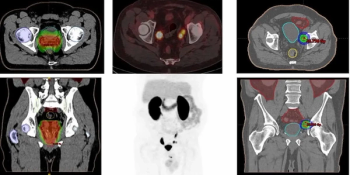

The PET/CT agent 18F-PSMA-1007 offered the highest surface under the cumulative ranking curve (SUCRA) out of nine radiotracers at the patient and lesion level for detecting clinically significant prostate cancer (csPCa), according to a meta-analysis.

Doubling of total tumor volume on PSMA PET/CT is 41 percent more likely to reduce overall survival in patients with metastatic castration-resistant prostate cancer (mCRPC), according to new research.

In patients with high-risk, hormone sensitive prostate cancer who had no evidence of metastasis on conventional imaging, PSMA PET revealed polymetastatic disease in 24 percent of patients and M1 disease staging in 46 percent of patients.